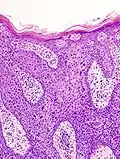

Image de la maladie de Bowen au microscope.

La maladie de Bowen est un carcinome épidermoïde (ou spinocellulaire) intra-épidermique (carcinome in situ), favorisé par le soleil et l'arsenic. Elle peut toucher la peau mais aussi les muqueuses[1]. Elle se présente sous la forme d'une lésion brun rougeâtre arrondie ou arciforme bien limitée dont la surface est un peu surélevée et squameuse[1]. Son diagnostic est histologique. Son évolution est très lente et la maladie présente un excellent pronostic de guérison. En revanche, en l'absence d'un diagnostic et d'un traitement approprié, elle évolue lentement mais sûrement vers un véritable carcinome épidermoïde invasif[1].